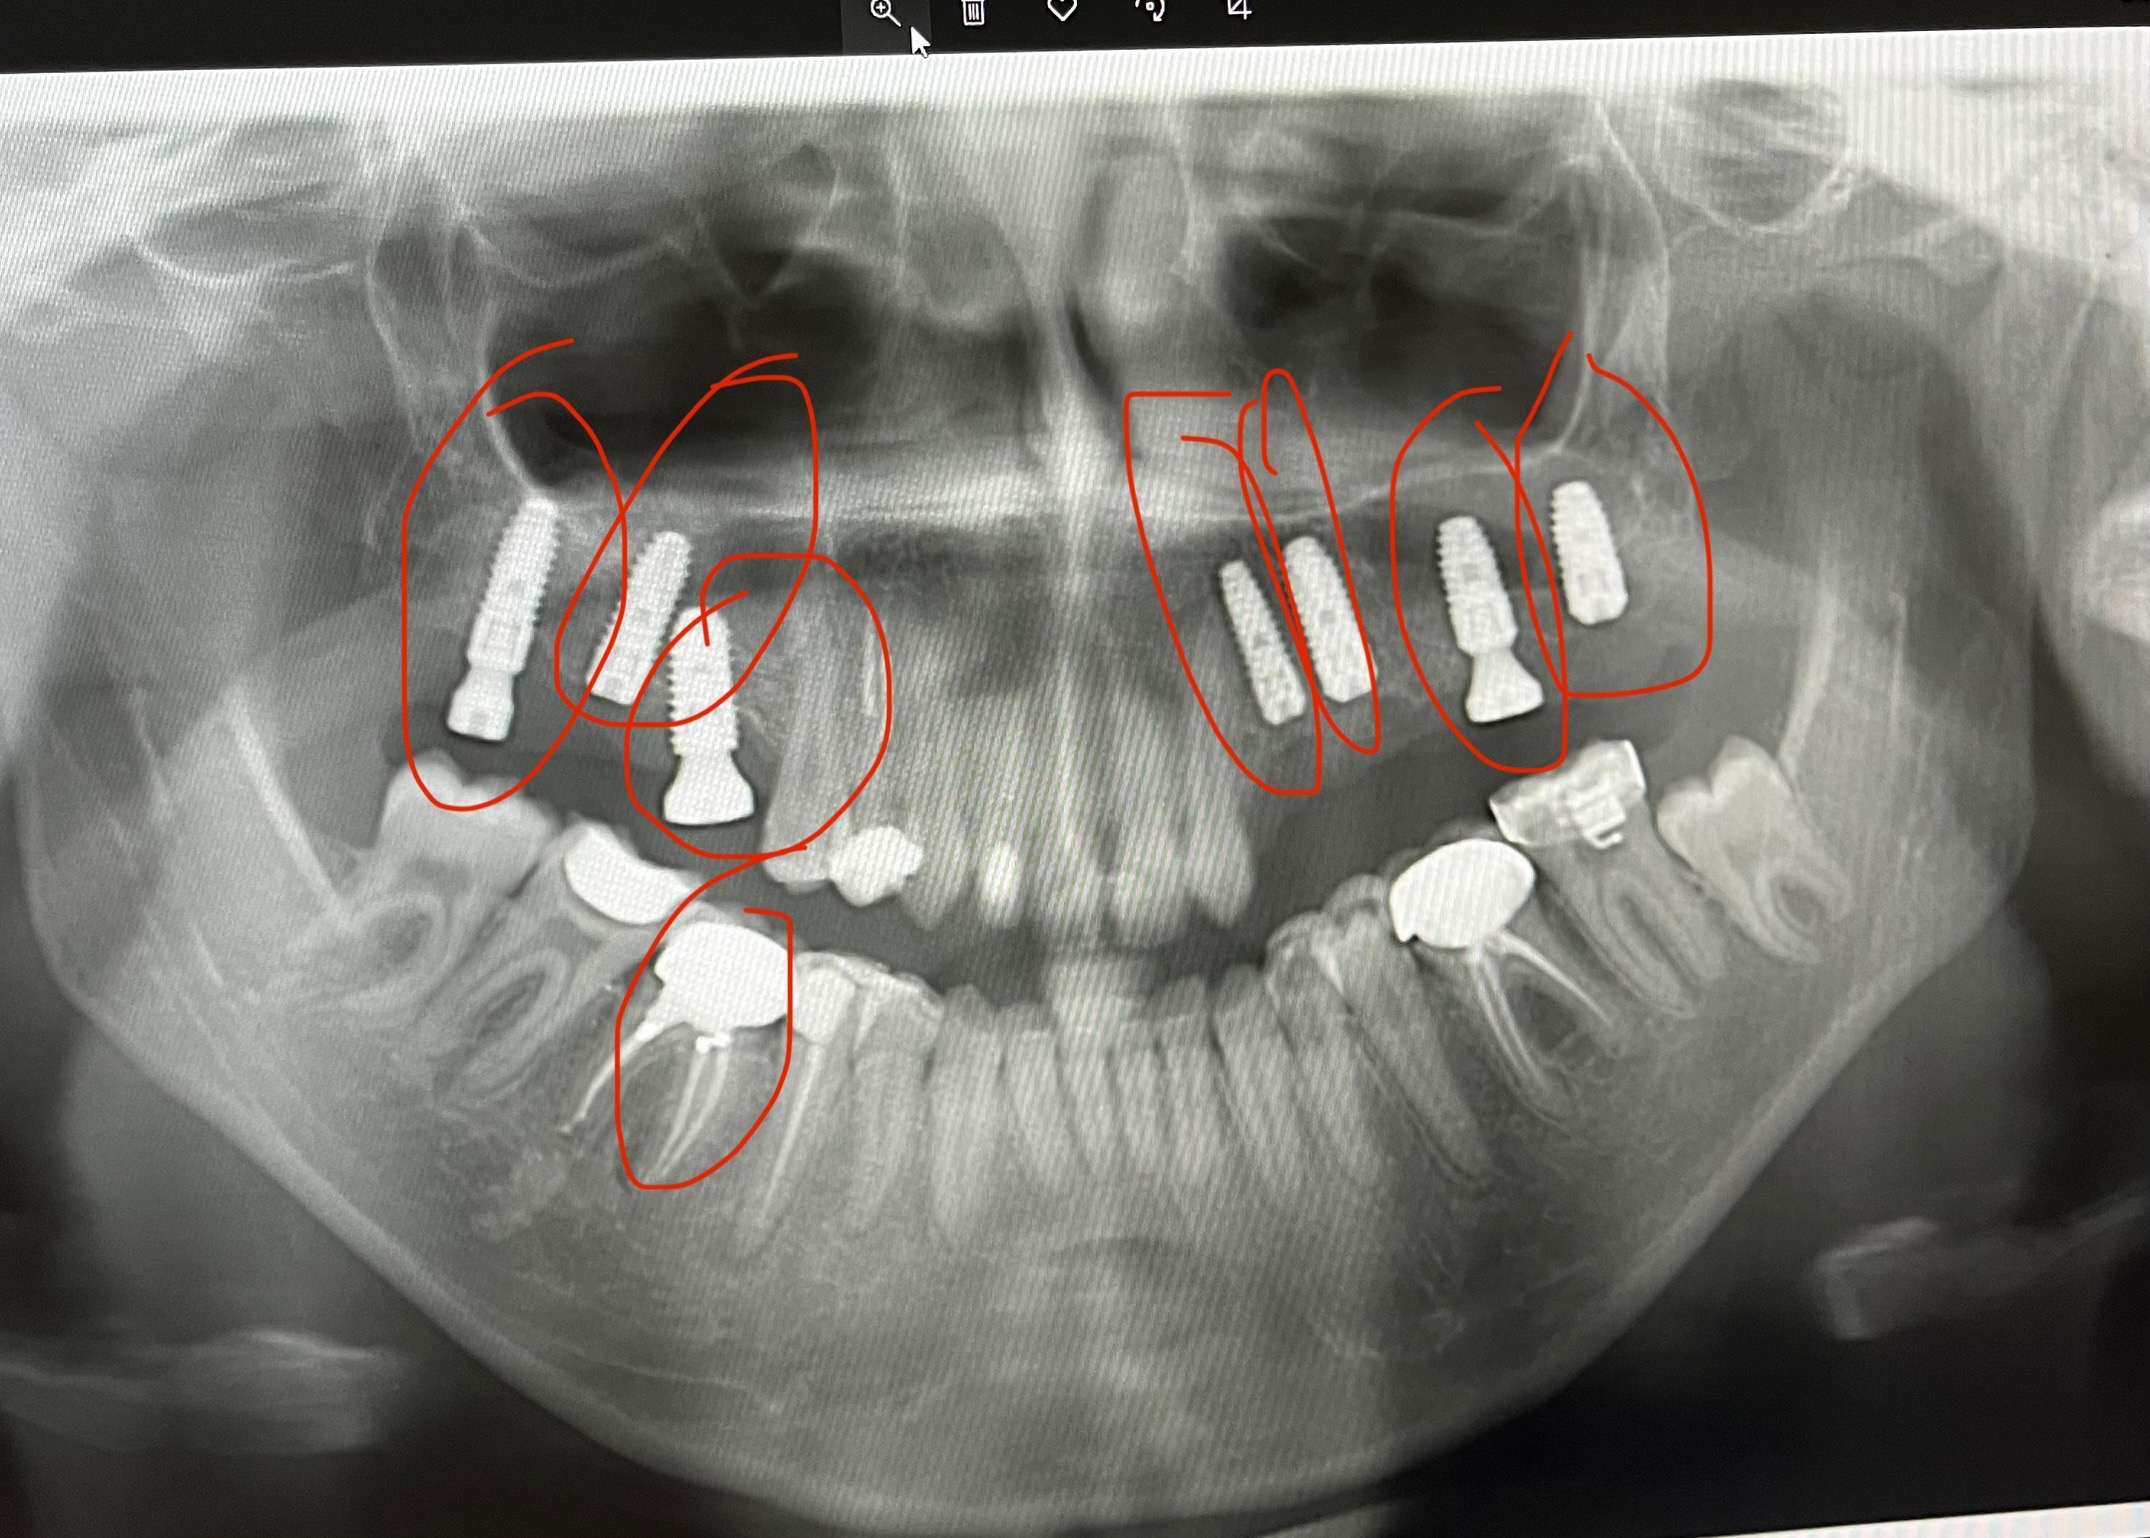

Several years ago, I went through a surgery in hopes of ending this struggle, but it ended in tragedy. The dentist performed the procedure carelessly, leaving both of my jaws misshaped and my implants misplaced. To make things worse, i couldn’t reach out to him and receive the missing parts of my implants to continue my treatment . After spending what I had on that failed procedure, I was left not only with greater health problems but also a heavy financial burden. For years I visited doctors, but many rejected my case due to its complexity.

Now, after a long search, I have finally found a specialist who can help me start over. But my case is no longer simple—the existing misplaced implants need to be removed, my jaws reconstructed, and bone grafting performed to replace the bone mass I have lost from years of delay. Several doctors will need to be involved in the surgery, making it far more complicated and costly than a normal double jaw surgery. This is my only chance to save my remaining teeth and prevent my condition from getting even worse.